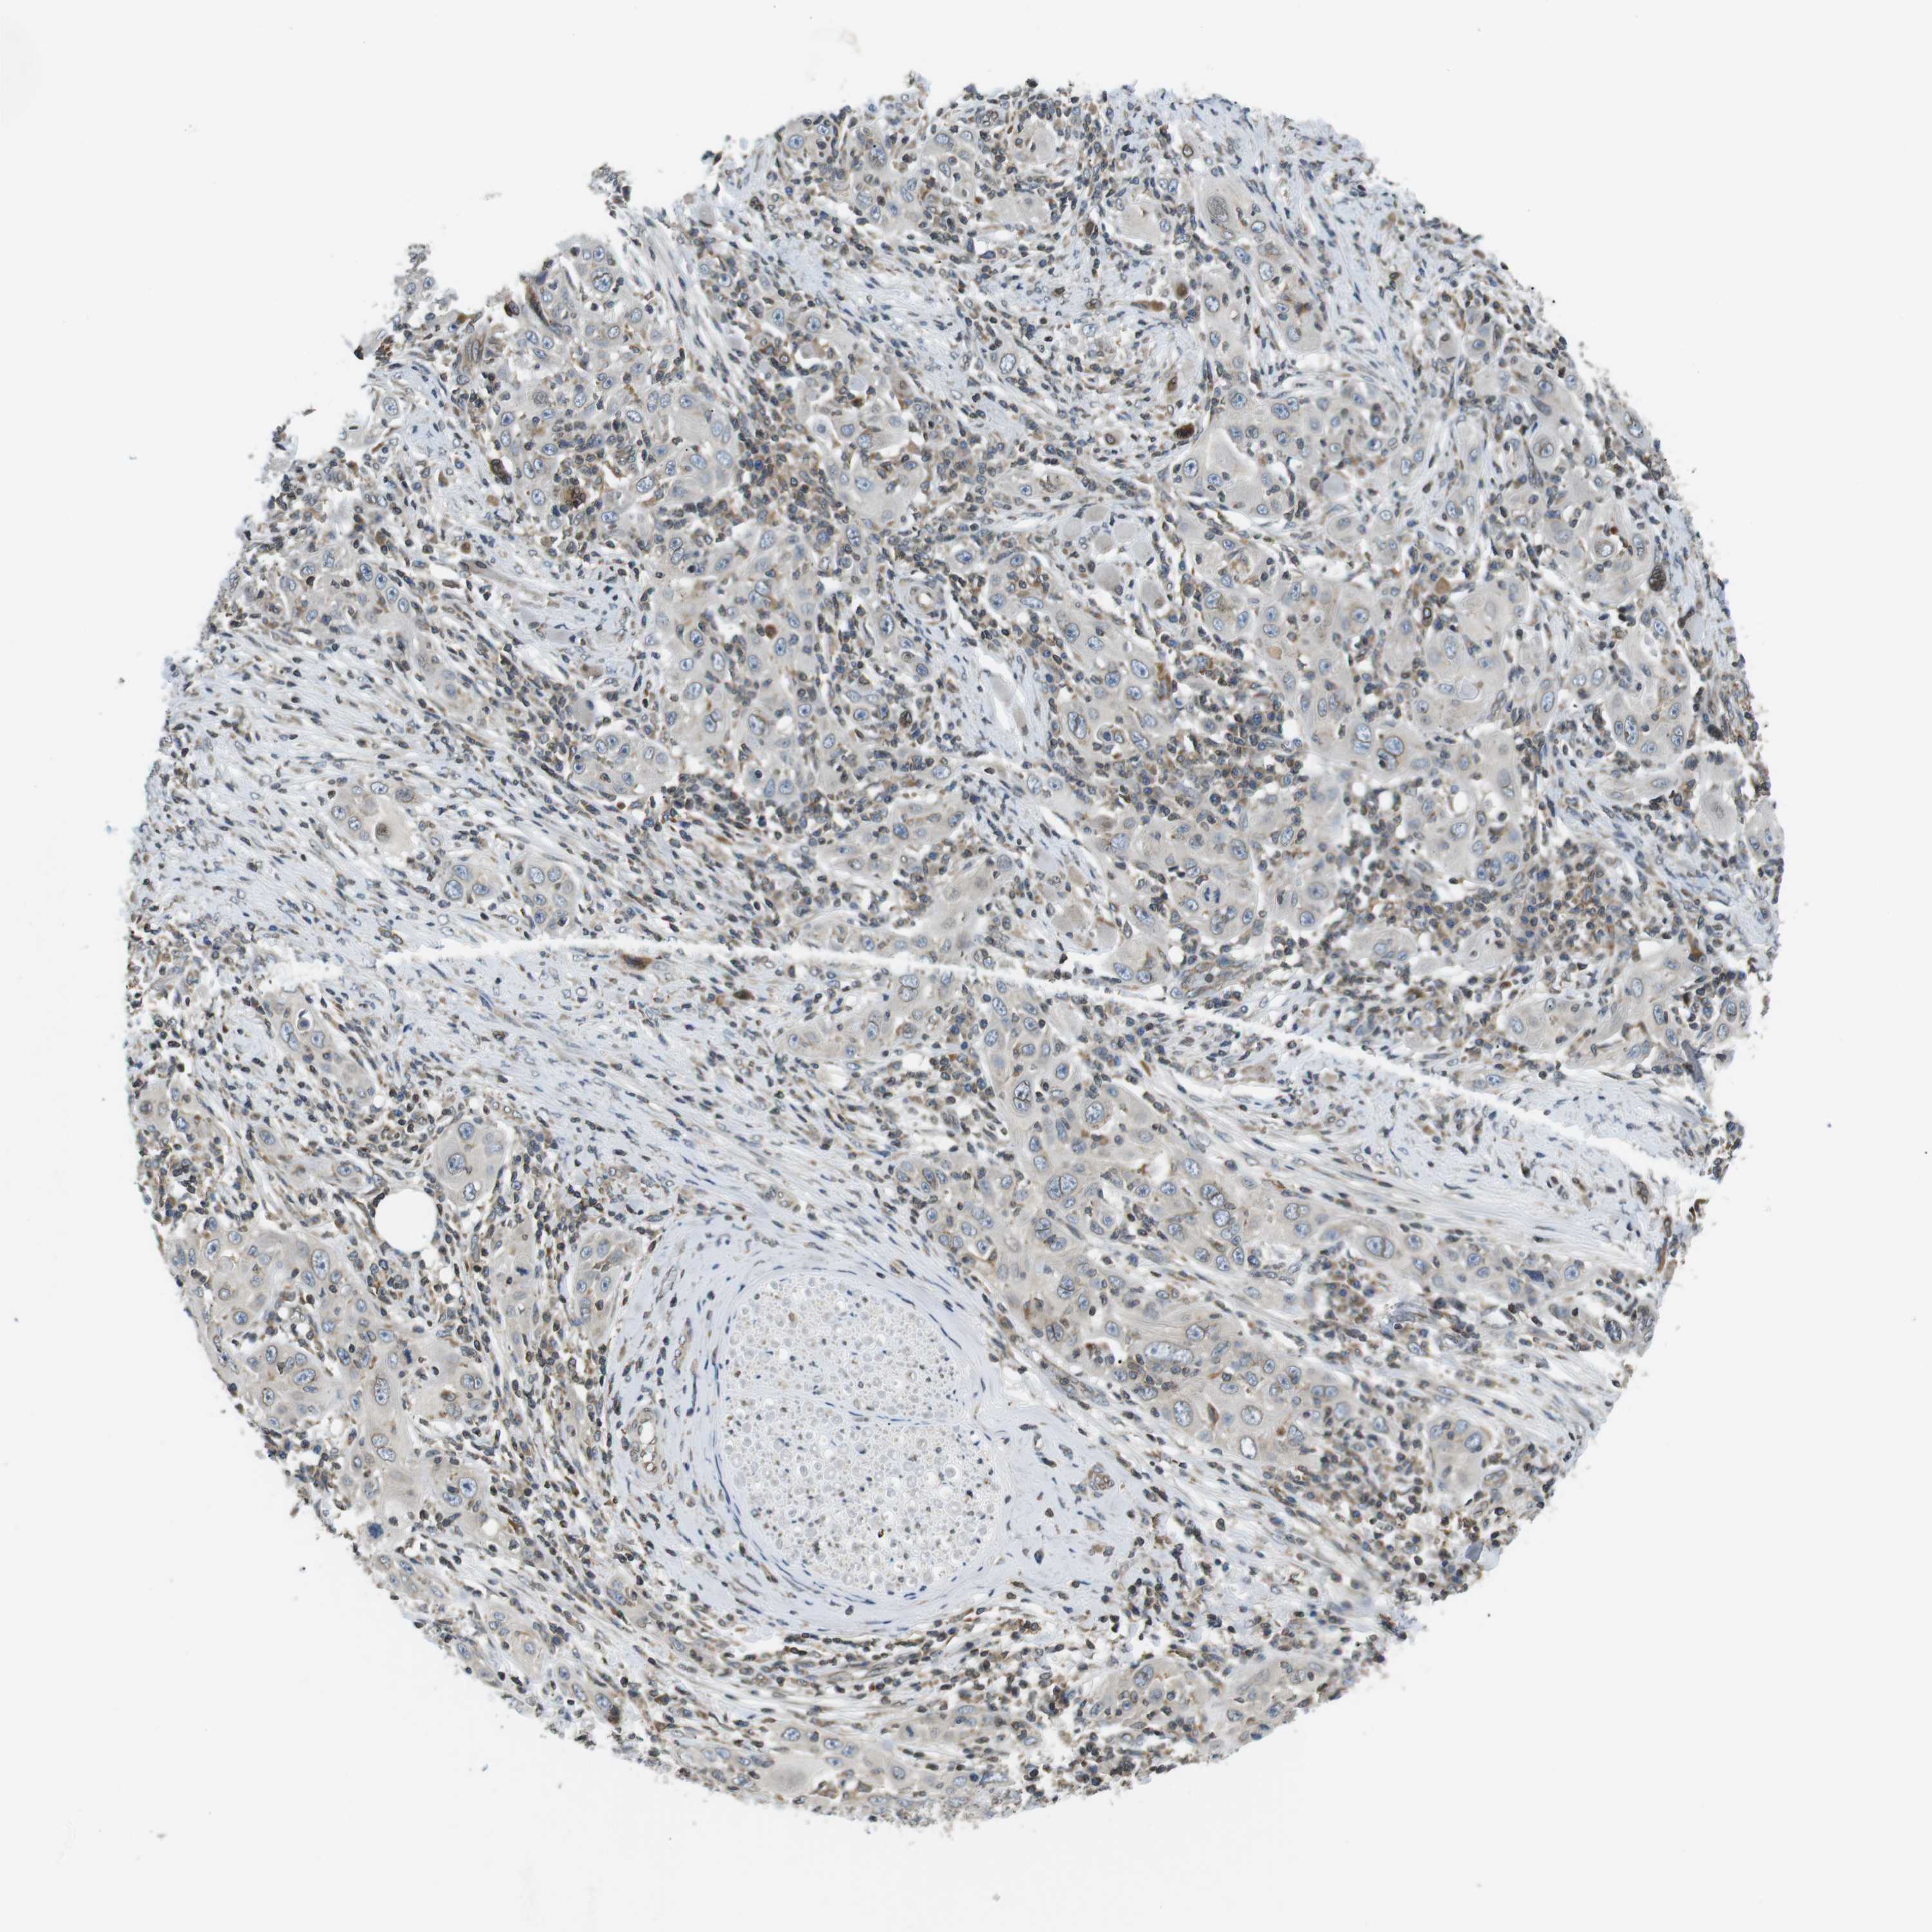

Basal cell and squamous cell cancer

SKIN CANCER - Protein expressioni

A mouse-over function shows sample information and annotation data. Click on an image to view it in a full screen mode. Samples can be filtered based on level of antibody staining by selecting one or several of the following categories: high, medium, low and not detected. The assay and annotation is described here.

Antibody stainingi

Antibody staining in the annotated cell types in the current human tissue is reported as not detected, low, medium, or high, based on conventional immunohistochemistry profiling in selected tissues. This score is based on the combination of the staining intensity and fraction of stained cells.

Each image is clickable and will lead to virtual microscopy that enables deeper exploration of all samples and also displays staining intensity scores, fraction scores and subcellular localization as well as patient and tissue information for each sample.

Antibody HPA000399

Antibody HPA015752

Staining

High

Medium

Low

Not detected

Intensity

Strong

Moderate

Weak

Negative

Quantity

>75%

75%-25%

<25%

None

Location

Nuclear

Cytoplasmic/membranous

Cytoplasmic/membranous,nuclear

Squamous cell carcinoma, NOS

Squamous cell carcinoma, metastatic, NOS

Basal cell carcinoma

Squamous cell carcinoma in situ, NOS

Adnexal tumor, benign